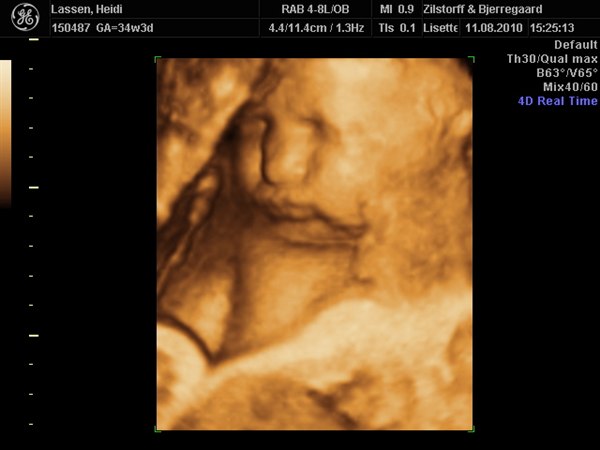

ja på det sidste billede af hende, ligner hun Emil når han blir utilfreds og sådan trækker trutmund/sur mine.

haha nåh ja det er rigtigt.. hun har en lidt sjov mund.. tror det er fordi hendes kinder er så store